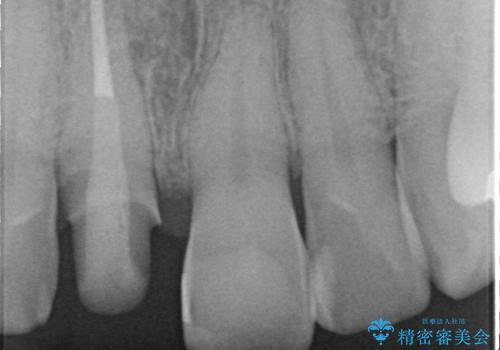

根管治療を行いそのままにしていると歯は、徐々に変色を来します。

感染の疑われる根管内に対し再度根管治療を行い、セラミッククラウンを作製することで審美性の回復します。